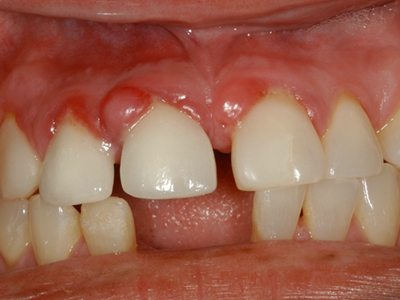

牙龈瘤多发于女性,以青年及中年人为常见,多发生于牙龈乳头部,位于唇、颊侧者较舌、腭侧者多,最常见的部位是前磨牙区。肿块较局限,呈圆形或椭圆形,有时呈分叶状,大小不一,直径由几毫米至数厘米。

肿块有的有蒂,如息肉状;有的无蒂,基底宽广,生长较慢,但在女性妊娠期间可能迅速增大。较大的肿块可以遮盖一部分牙及牙槽突,表面可见牙压痕,易被咬伤而发生溃疡,伴发感染。随着肿块的增长,牙槽骨壁逐渐被破坏,牙可能发生松动、移位。